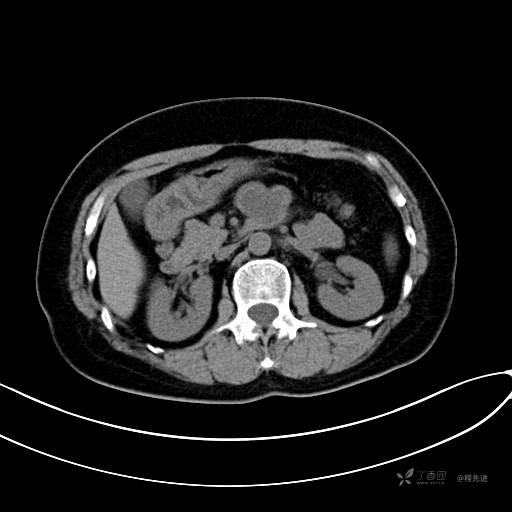

CT增强静脉期